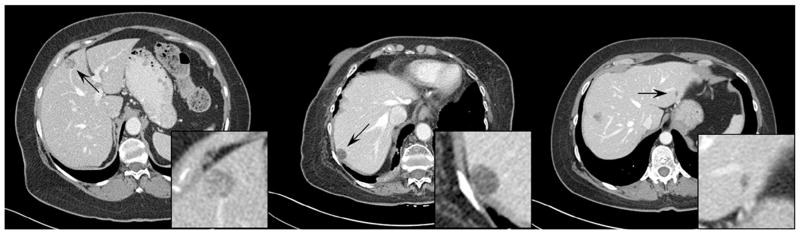

- insertion results(插入不同数量的探针)

- 第一行是一个case。第一张:包含真实的三个探针;第二张:包含真实的四个探针;根据前两张:第三张在第一张上面插入了一个探针。

- 第二行是一个case。第一张:包含真实的一个探针;第二张:包含真实的四个探针;根据前两张:第三张在第一张上面插入了三个探针。

- insertion results(在不同域插入探针)

- 从左到右:图像域插入探针(没有伪影),投影域插入探针,两者的为彩图